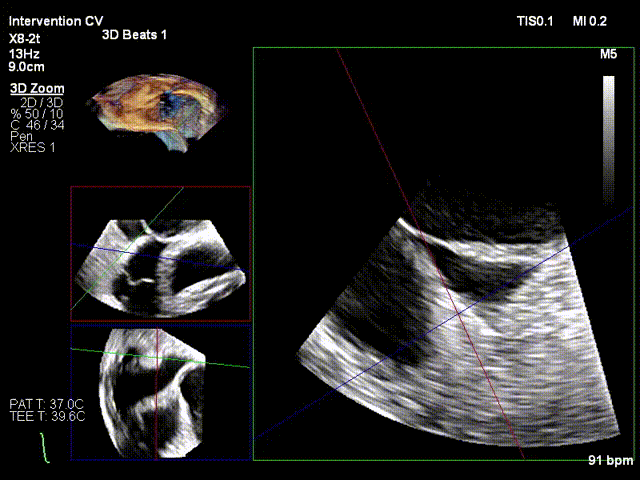

After the patient was placed under general anesthesia, the jugular vein was punctured intraoperatively to establish surgical access. An 18Fr delivery sheath was advanced along a stiff guidewire to the mid-inferior right atrium, and the delivery system was introduced under ultrasound guidance. A 12T K-Clip® device was implanted at the posterior annulus, and another 12T K-Clip® device at the anteroposterior annulus respectively. The angle between the device and the annulus plane was adjusted through catheter deflection and rotation, directing the tip of the clip device to the target position. The anchoring component was deployed into the annulus under ultrasound MPR mode; after confirming stable traction, the clamping arms were opened and apposed to the annulus, followed by retraction of the anchoring component to close the clamping arms for annuloplasty. The surgical effect was evaluated as satisfactory, and the clip components were then released.

Opening the clamping arms, adjusting the direction and apposing to the annulus

Releasing the clip after closure